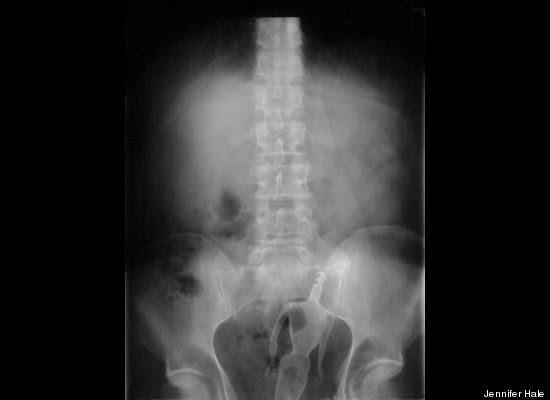

"Stack Up!" es una muy divertida colección de 100 imágenes de rayos X que muestra cuerpos extraños ingeridos o insertados en el cuerpo humano, tanto por accidente o de forma voluntaria, aunque se haga difícil imaginar el motivo de algunas de tales inserciones.

Los autores del libro -dos psiquiatras y un médico de sala de emergencias- aseguran -sin mucha originalidad pero con conocimiento de causa, que la imaginación humana no tiene límites. Esta afirmación es aplicable tanto a la calidad y variedad de objetos tragados o incorporados al cuerpo, como a los motivos o excusas utilizados para justificar la presencia de dichos objetos.

"Hay gente que hace cosas realmente imprudentes, y luego trata de racionalizarlas", advierten los autores en la solapa del libro, destacando precisamente la imaginación humana para "dar con usos imprevistos para objetos de la vida cotidiana".

"Tenía las manos ocupadas", "me caí encima", son algunas de las excusas que los profesionales de la salud escuchan de los pacientes que llegan a los hospitales con "cuerpos extraños extrañamente metidos en el cuerpo".

Redactado de manera humorística, el libro se pregunta cómo un teléfono celular puede haber ido a parar al sitio de la anatomía del propietario donde nunca da el sol, respondiéndose que, probablemente, estuviera en modo vibrador.

"Hallar un termómetro atascado en el recto de un adulto puede resultar corriente. Pero ¿Qué se puede decir de una muñeca Barbie, perteneciente a su hija de seis años?", se preguntan los autores, añadiendo el consejo infaltable: no hagan esto en casa.